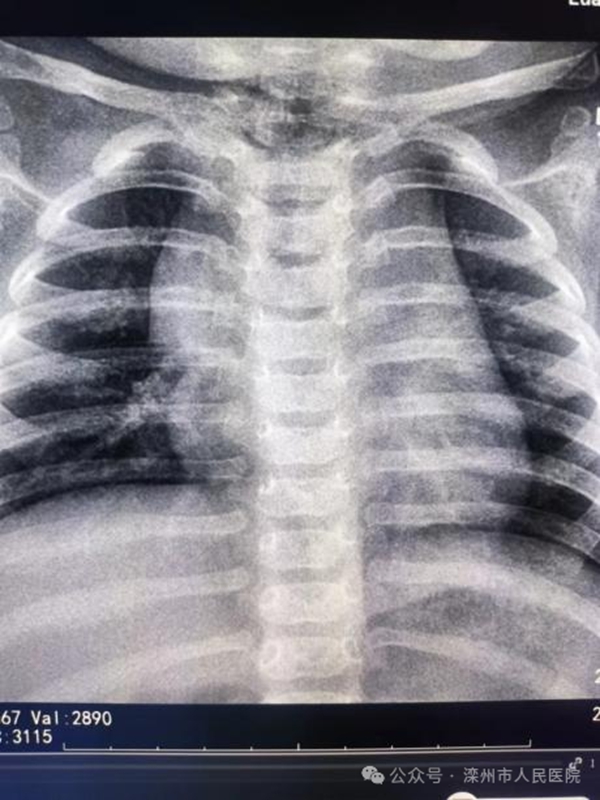

1帆船征

正常胸腺向右側(cè)延伸增大,形似船帆。

圖1:患兒右上肺內(nèi)帶軟組織密度影,右側(cè)胸腺外側(cè)與下部邊緣光滑整齊,形成「帆船征」。